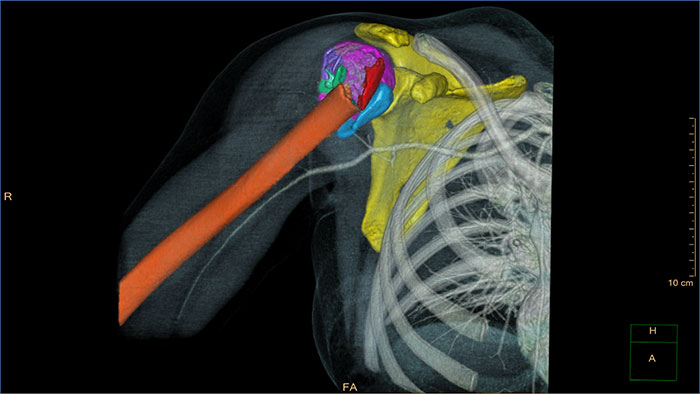

CT Acute MultiFunctional Review (AMFR) allows the clinician reading trauma cases to remain within one comprehensive post-processing application to accomplish the diagnosis of trauma patients that were scanned with CT.

- Viewing stage for trauma assessment. - Vascular assessment tools. - Automatic spine curve reformation and vertebra labeling. - Interactive pre-surgical MSK. - Multifunctional Findings Navigator to create, manage,

and convey findings.